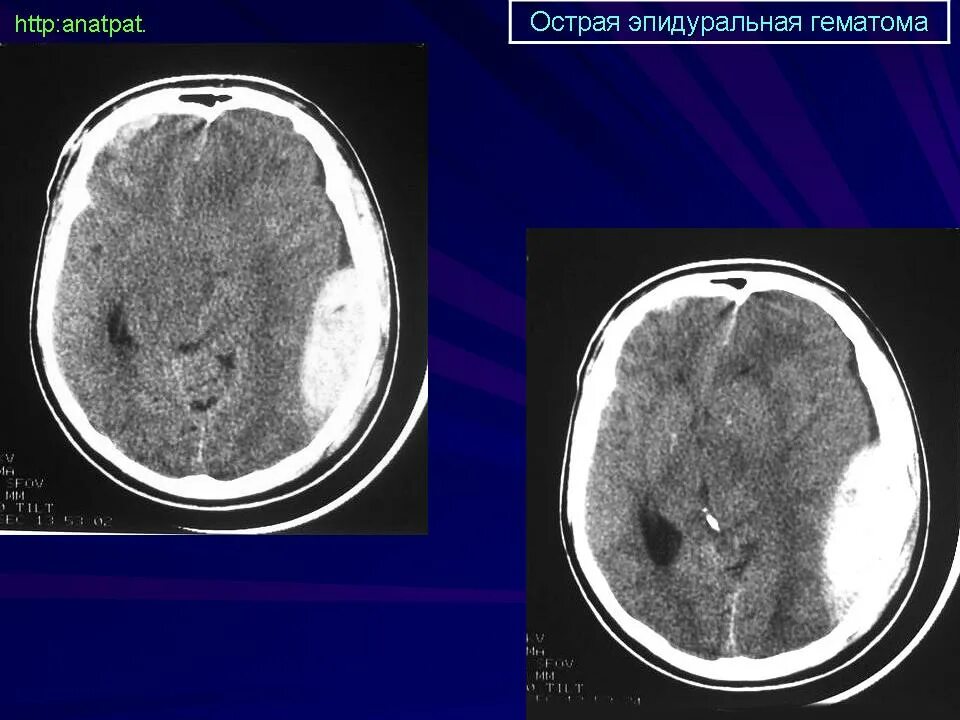

Объем гематомы на кт